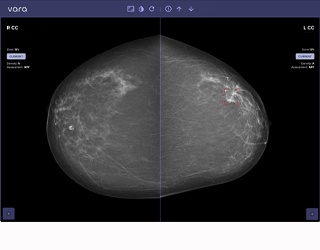

Im Vergleich zur Mammographie liefert das System eine überlagerungsfreie 3D-Bildgebung. Gegenüber der MRT entfallen die Gadolinium-Kontrastmittelgabe sowie die aufwändige Lagerung und Untersuchungsdauer. Und im Unterschied zu sogenannten „Cone-Beam- Systemen“ basiert das nu:view auf Spiraltechnik mit höherer isotroper Auflösung bis zu 90 μm und erhöhter Projektionsdichte.

Überlagerungsfreie 3D-Bildgebung